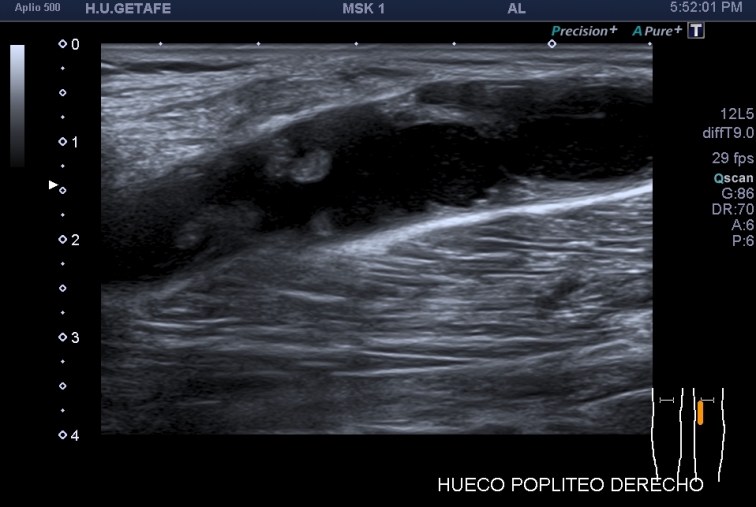

La imagen 3 y 4, como son tan nítidas, puedes ver como el quiste de Baker no es un quiste de Baker simple, la pared es grosera, tiene septos y ecoestrusturas que hacen pensar que el quiste ha podido sufrir algún sangrado. Hay que descartar la formación de lesiones sólidas o polos sólido en los quistes (usando doppler), por norma general, en todos aquellos quistes que estudiemos, en otras localizaciones, por ejemplo, en la mama, en el abdomen, etc.